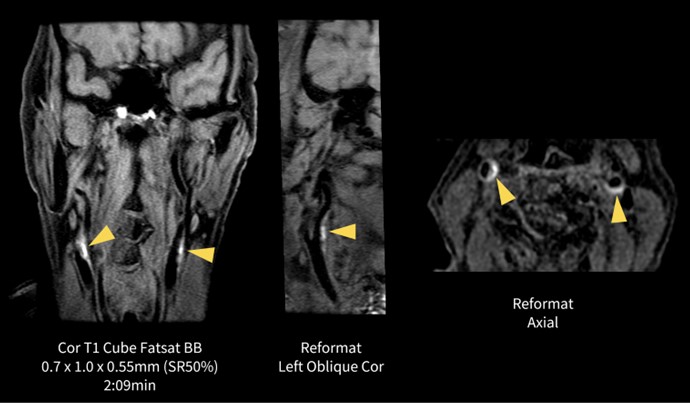

眼窩は32-Channel Head Coilで撮像している。FOV15cmでスライス厚も2.5mmと高分解能な撮像条件であるが、SNRは十分に担保されつつ、腫瘍と視神経や内直筋、外直筋との位置関係も明瞭に描出されている。注目していただきたい画像はCoronal STIRである。STIRはSNRが下がりやすいシーケンスの一つであるが、AIR™ Recon DLのおかげでノイズも目立たずに短時間で撮像することができた。

図3.眼窩(眼窩内腫瘍)